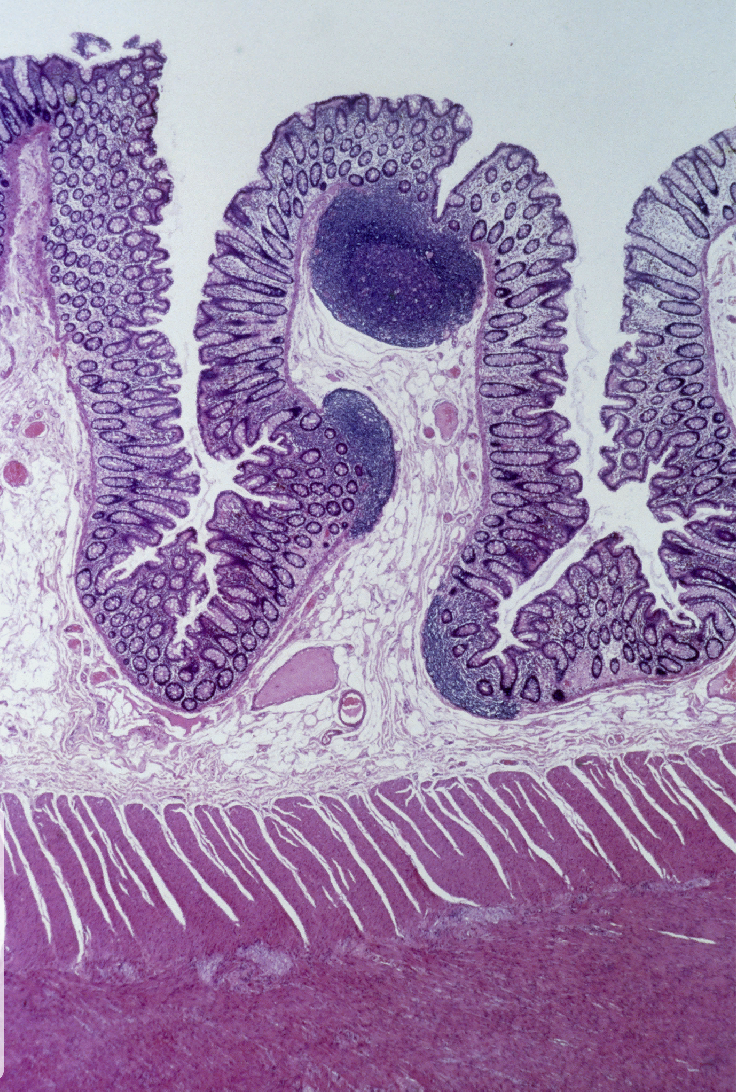

List the layers in the small intestine

Mucosa- ciliated pseudostratified columnar epithelium